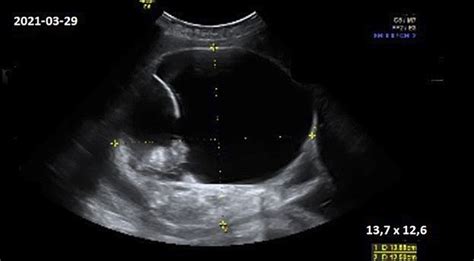

- Netaisyklinga vaisiaus padėtis gimdoje (pvz., sėdmeninė, skersinė), kurios nepavyksta koreguoti.

- Placenta previa (kai placenta visiškai ar iš dalies dengia gimdos kaklelį).

- Pavojinga vaisiaus būklė, nustatyta nėštumo metu (pvz., ryškus augimo atsilikimas).